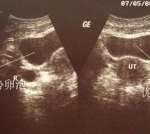

一般检查项目有:女方——常规检查,盆腔检查,B超,血激素,免疫抗体,病毒检查,造影,染色体等。男方——精液常规,性激素,染色体等。建议您还是正规医院为宜,希望我的答复能对你有所帮助,祝你生活愉快!一般费用为3-5万。